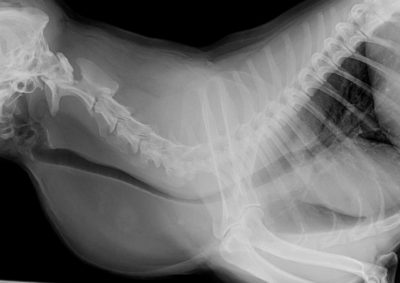

猫の尿道閉塞